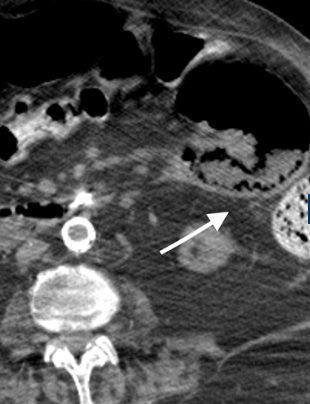

Our patient had a multicystic lesion in the head of the pancreas suggestive of a serous cystic neoplasm.  She also had multiple cystic pancreatic tail lesions thought to represent intraductal papillary neoplasms.  In addition, she had a renal sinus cyst on the left which can mimic hydronephrosis.